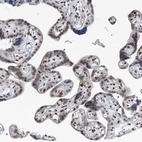

Immunohistochemical staining of human testis shows strong nuclear positivity in cells in seminiferous ducts.